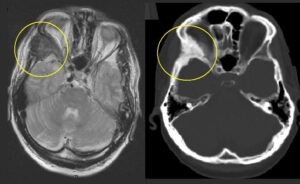

- Scintigrafia planare vs. SPECT/CT: per il calcolo della frazione di shunt polmonare (LSF), la scintigrafia planare è stata storicamente la modalità più utilizzata. Tuttavia, tende a sovrastimare la LSF rispetto alla tomografia a emissione di fotone singolo (SPECT/CT). Per questo motivo, la SPECT/CT è raccomandata per calcoli dosimetrici più accurati. L’adozione della SPECT/CT non è solo una questione di precisione numerica; consente una dosimetria personalizzata a livello “voxelare“, fondamentale per i modelli a partizione e per massimizzare la dose al tumore minimizzando la tossicità al parenchima sano, un obiettivo irraggiungibile con la stima bidimensionale della scintigrafia planare. Per la verifica della distribuzione post-trattamento, la Y90 PET/CT è considerata la modalità migliore, ma anche la Bremsstrahlung SPECT/CT è un’alternativa accettabile e più accessibile;